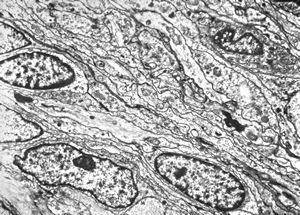

F,50y. | progressive multifocal leukoencephalopathy- viral particles in a glial cell

F,50y. | progressive multifocal leukoencephalopathy- viral particles in a glial cell

F,50y. | progressive multifocal leukoencephalopathy- viral particles in a glial cell